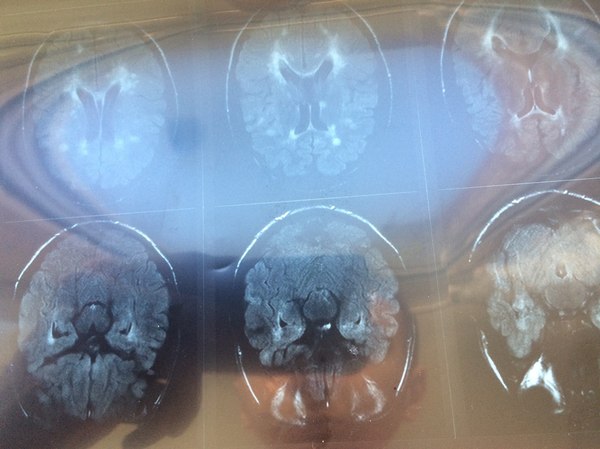

Тут было не всё так просто. Да, МРТ было у меня на руках (вот пара снимков оттуда. Несимметричные светлые пятна - очаги или бляшки). Немного очагов - был момент ремиссии.